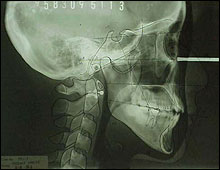

@ L - Cephalogram

1. Depth of curve of Spee in mm (-)

2. MM discrepancy space in lower arch

3. MM to upright of lower incisors

5. ANB change (1mm per degree)

6. Mandibular plane angle is extreamly

high 36 as 1. |